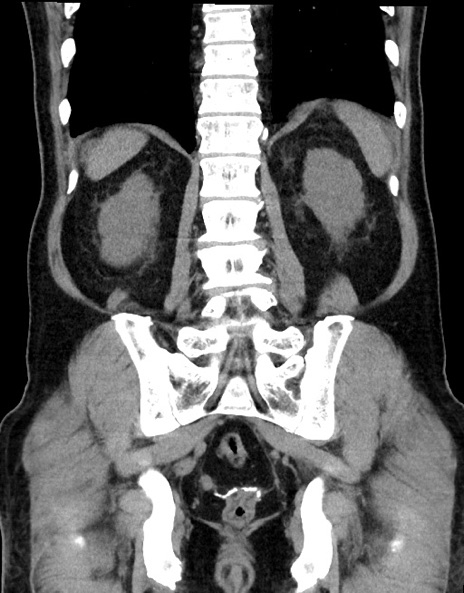

症例15(冠状断像)

【症例】70歳代男性

【主訴】腹痛

【現病歴】今朝から腹痛あり。全体的に痛い。特に左上の方。排ガスが今日はない。冷や汗が出る。

【既往歴】直腸癌術後

【身体所見】左側腹部〜上腹部に圧痛あり。腹膜刺激症状明らかなではない。軽度反跳痛。左下腹部に術後瘢痕あり。

【データ】WBC 7700、CRP 0.02